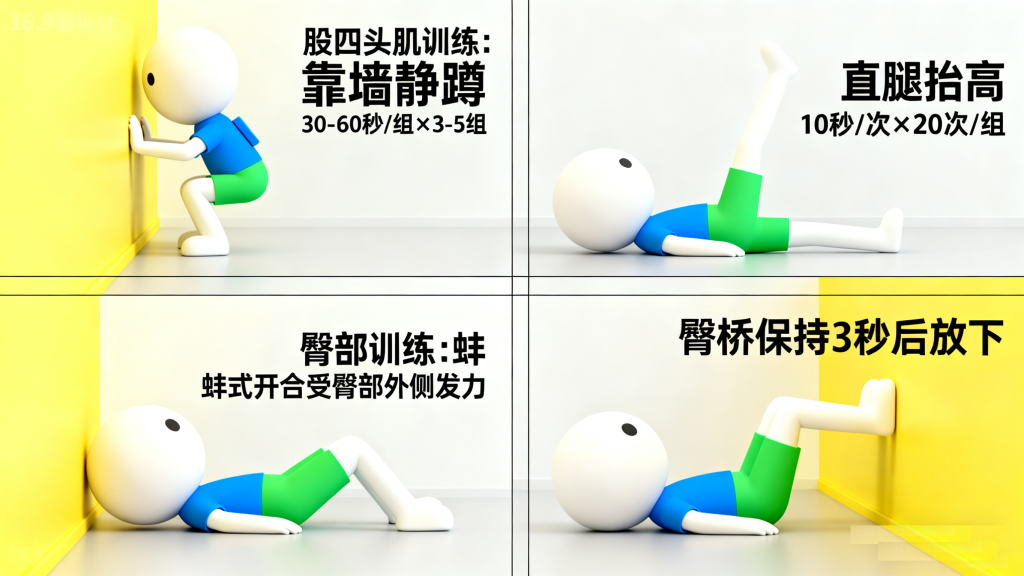

股四头肌训练:靠墙静蹲(背部贴墙,膝盖弯曲不超过90°,保持30-60秒/组,做3-5组)、直腿抬高(平躺,腿伸直抬高至与地面30°,保持10秒/次,做20次/组)。

臀部肌肉训练:蚌式开合(侧卧,膝盖弯曲,缓慢打开和闭合膝盖,感受臀部外侧发力)、臀桥(平躺,双腿弯曲,臀部抬起至身体呈直线,保持3秒后放下)。